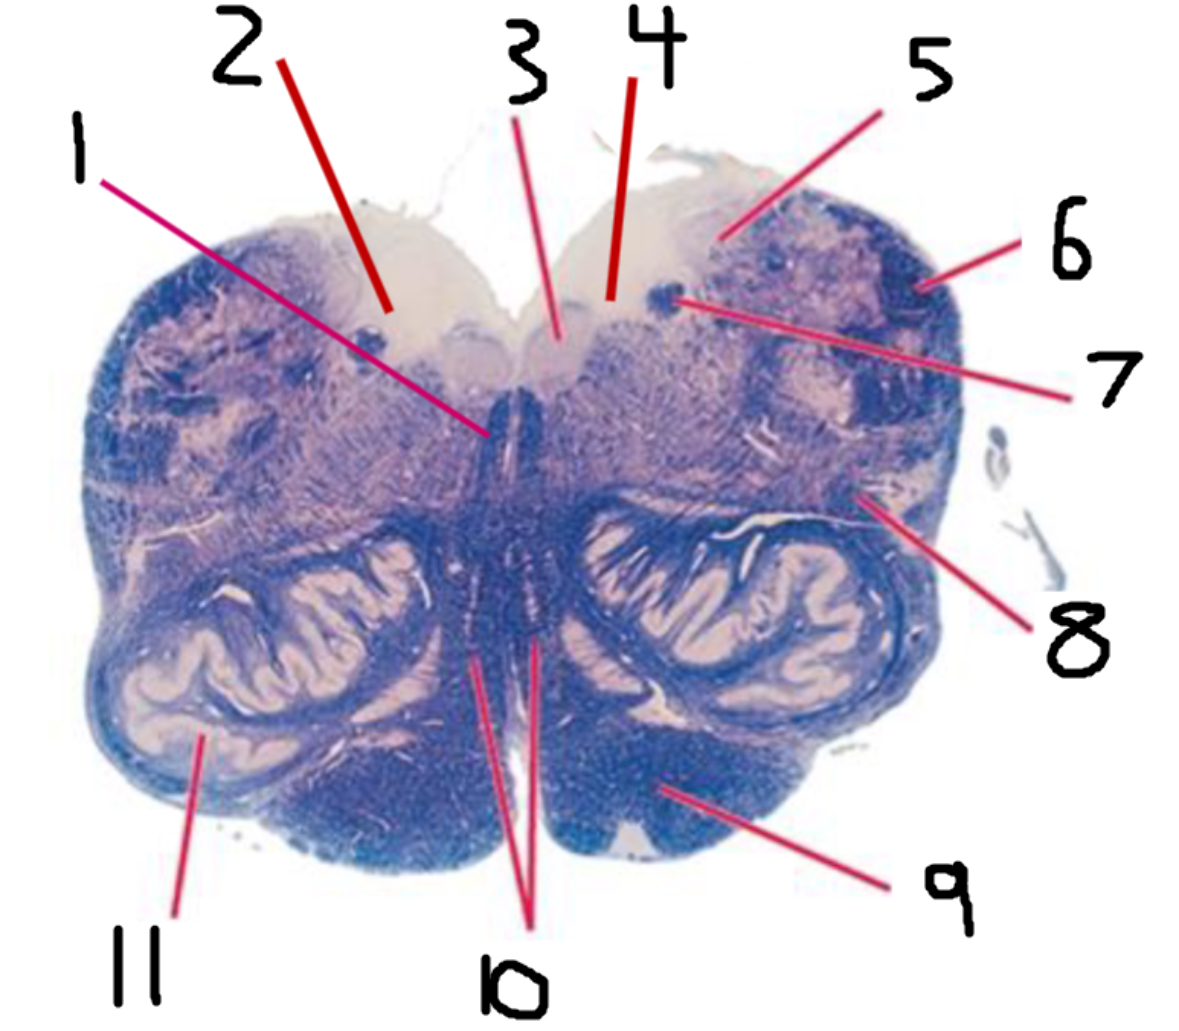

#1 is the:

Cingulate Gyrus

#2 is the:

Septum Pellucidum

#3 is the:

Lateral Ventricle

#4, #7, and #12 is the:

Fornix

#5 is the:

Third Ventricle

#6 is the:

Anterior Commissure

#8 and #11 is the:

Amygdala

#9 is the:

Hypothalamus

#10 is the:

Mammillary Body

#13 is the:

Insula

#14 is the:

Globus Pallidus

#15 is the:

Putamen

#16 is the:

Internal Capsule

#17 is the:

Caudate

#18 is the:

Corpus Callosum